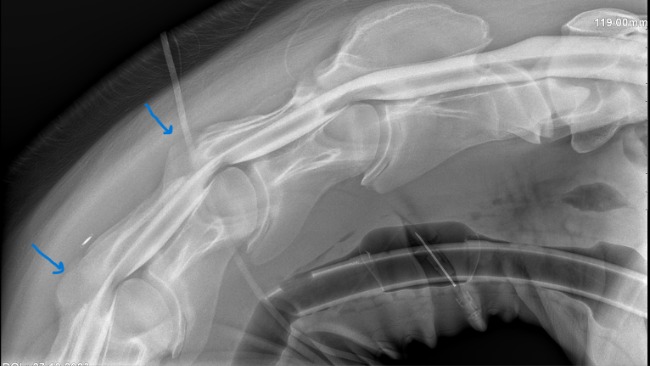

Cześć nazywam Się Tiara Mam niecałe dwa lata ... tzn z tym imieniem. To tak mnie wołają tylko na to reaguje - prawdziwego nie lubie 😘 Urodziłam się tu w Polsce Jestem ślązaczką z krwi i kości ..😍 A skoro już o kościach mowa.... Moja nowa pani kupiła mnie od mojego hodowcy .. pomogli jej ludzie o wielkich sercach ❤️ a później tzn w tym samym dniu jak mnie zabrała to dala mnie do kliniki . Gdzie ciocie i wujkowie zrobili mi jakieś dziwne rzeczy . Mówili coś o sprawdzaniu moich kości Nazywali to BADANIAMI. Ja to w sumie nie wiem.. spałam smacznie za każdym razem a później słyszałam "obudziła się " chyba wszyscy czekają ciągle na moje pobudki 🤩 Ale później przez dłuższą chwilę nie dają jeść a ja to tak nie lubię... 🫣 Ostatnie moje przebudzenie wsrod wujkow byłi dzisiaj w piątek. ...I po tym przebudzeniu jakoś bardzo się cieszyli .. co oni myśleli że ja zasnęłam na amen czy co ? 🫠 Zaraz jak wstałam zadzwonił jeden z wujków do mojej pani mamy ... I powiedział że mogę mieć operacje a później rehabilitacje ale ze koszta tego są bardzo duże😪 i że jest jakieś niewielkie ryzyko bo nie wiedzą jak długo mam uszkodzony rdzeń... pani Mama mówiła że chciałaby walczyć za wszelką cenę ale ze nie ma tyle pieniędzy na tą chwilę... Pani mama chyba płakała 😪 A ja nie wiedziałam o co chodzi jednak zrobiło mi się smutno m. Tu w klinice tak ładnie mnie drapała i glaskala przed swoim wyjściem i mówiła że jestem tu tylko na chwilę i że wróci... Pani mamo .. Ja też chcę.. Ja chcę byś wróciła byś mnie nie zostawiła.😭. Nie chcę już się chwiać a podobno tą operacja ma to naprawić ... Ma naprawić uszkodzone kręgi szyjne .. ktore sprawiaja mi teraz duzy bol i przez ktore nie moge chodzic tak jakbym chciala 😭. Wujek doktor mówił że cierpię na wobblera z ataksja ale ze mogę żyć normalnie ale tylko po operacji ... Potrzebuję chyba waszej pomocy ludzi o dobrym sercu by żyć w moim nowym domu ... Poniżej zdjęcie Rtg mojej szyi Błagamy ratujmy wspólnie Tiare 🙏🙏 " W załączonym obrazie widać ucisk na rdzeń kręgowy w obszarze przestrzeni C3-C4 oraz C4-C5 widoczny jako ponad 50% redukcja szerokości dorsalnej kolumny kontrastu w projekcji w wymuszonym zgięciu szyi." Ucisk kregow powoduje ataksje . Pierwszy termin operacji planowany na 06.11 23. Pozniej mozna umawiac inny termin ale koszt doby w klinice to 80zl dodatkowo czas dziala bardzo na niekorzysc dla Tiary 😭.. Koszt operacji i rehabilitacji lekow trzeba liczyc w przedziale 25 tysiecy ... dodatkowy tysiac jest na reklamy na portalach. BLAGAMY WSZYSTKICH O WSPARCIE Tiara zostala uratowana przed handlarzem teraz przyszlo ratować ją przed smiercią w zwiazku z chorobą... zawalczmy jeszcze o tą wojowniczke 🙏🙏😪